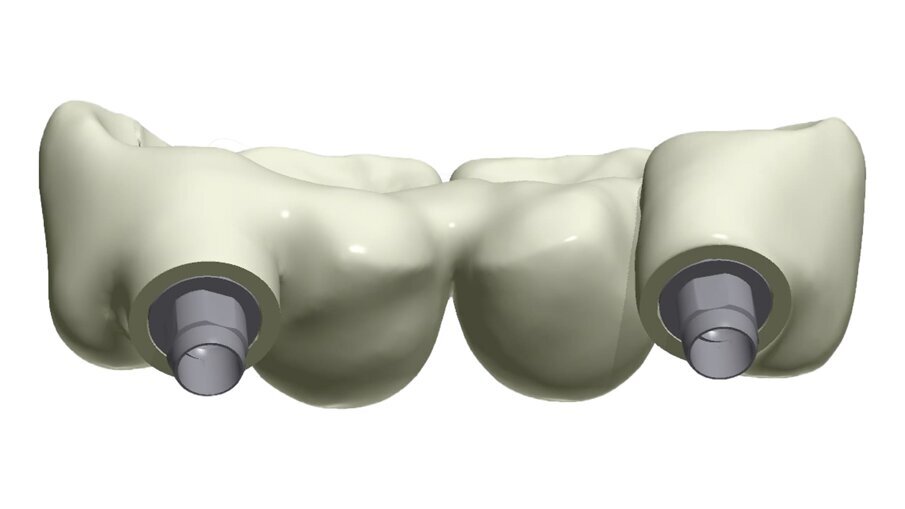

I dati raccolti sono molti ma la procedura digitale consente di sommarli e confrontarli senza limiti e indicando le possibili migliori e correzioni lungo il percorso. Dopo un breve periodo di condizionamento dei tessuti (Fig. 30) rileviamo l’impronta master per la finalizzazione ultima della riabilitazione protesica. L’impronta degli elementi naturali viene rilevata posizionando dei fili detrattori secondo la tecnica del doppio filo mentre per gli impianti verranno usati gli scan body dedicati (Fig. 31). Le potenzialità digitali consentiranno di avere una stabile lettura della posizione di centrica rilevandola prima della rimozione dei provvisori e sovrapponendola a provvisori rimossi (Fig. 32). In laboratorio l’odontotecnico realizza i modelli (Figg. 33, 34) sovrappone le immagini (Fig. 35) e raccoglie gli elaborati dei vari passaggi che porteranno alla finalizzazione del progetto digitale (Figg. 36, 37). Gli impianti in Zirconia non offrono molte soluzioni protesiche, è importante che il loro posizionamento tenga conto di quest’aspetto mettendo l’odontotecnico nelle condizioni più favorevoli (Fig. 38). Questa sistematica prevede l’uso di un moncone in titanio cementato nella struttura protesica che permette l’avvitamento all’interno dell’impianto. Nella connessione implantare è presente un’intercapedine dove alloggia il collarino in titanio del T-base totalmente inglobato all’interno della zirconia, evitando comunicazioni coi tessuti adiacenti. Va comunque considerato l’aspetto tecnico importante legato allo spessore della struttura in zirconia che deve avvolgere l’intero moncone in titanio. (Fig. 39, 40).

Fig. 38_Il ponte tra gli impianti in Zirconia rappresenta un progetto complesso tra il rispetto del tunnel mucoso, l’anatomia vestibolare, gli spazi circolari e il foro per l’avvitamento coronale.

Fig. 39_Il progetto digitale consente all’odontotecnico di definire a livello circolare i limiti e gli spessori di rispetto della Zirconia.

Fig. 40_Anche la scelta dell’altezza del t-base è un’altra determinate al manufatto finale.